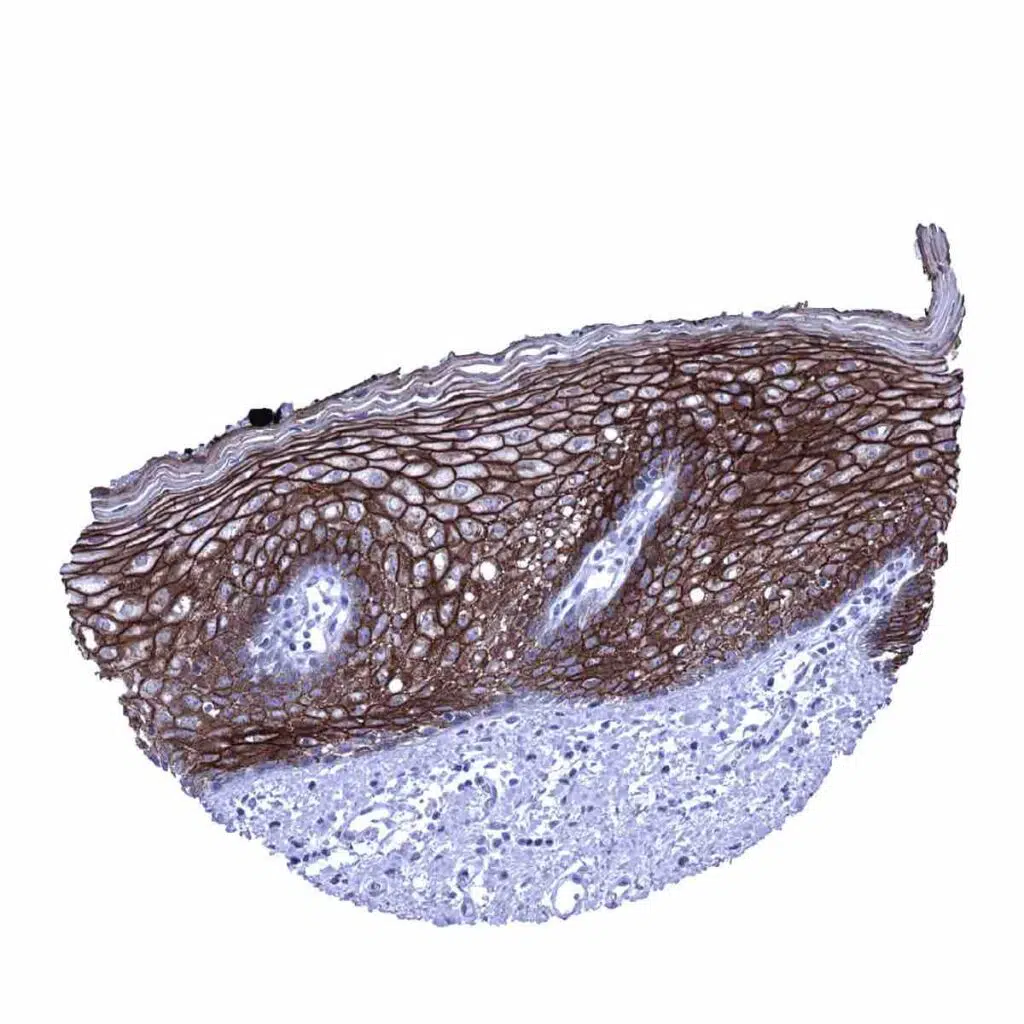

Skin – Strong membranous desmoglein 1 immunostaining of the squamous epithelium of the skin. A slight decrease of staining occurs in the most superficial cell layers